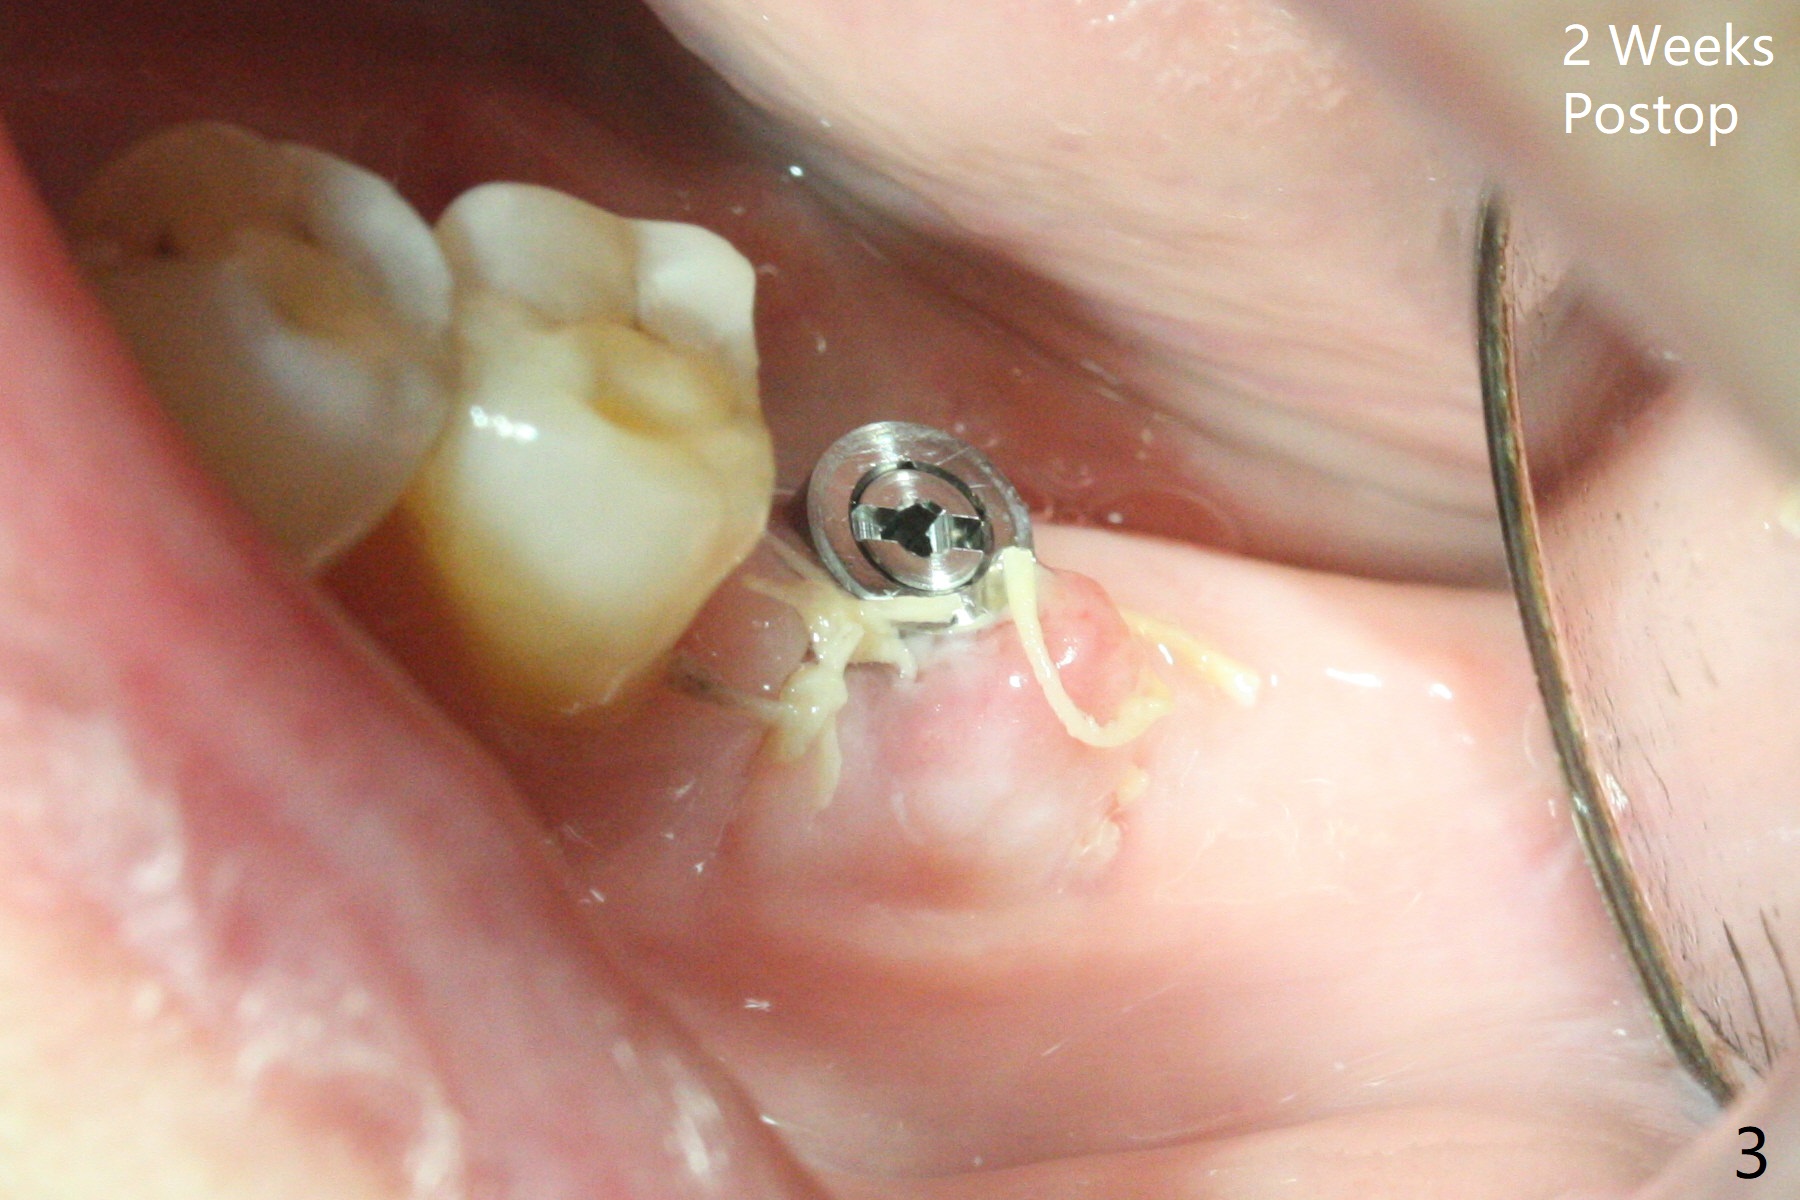

Following light use of 4 mm tissue punch, a buccal incision is made and raised. After 4x8.5 mm drill with 10.5 mm offset at #19, 4.5 mm cortical drill is used for 2/3 length to take care of the thick dense lingual plate (overprep). The remaining apical 3 mm osteotomy is underdrill (3.5 mm). After try-in of a 4.5x14 mm tissue-level dummy implant, a same-sized definitive one obtains 35 Ncm torque (Fig.1). Following 3-4 more turns, the torque reaches 45 Ncm (Fig.2) with the distal thread covered (<) and autogenous bone graft placed in the distal defect (*). A 4x3 mm unipost is placed to keep periodontal dressing in place. Clinically the implant is placed within bone boundary buccolingually. The new implant seems necessary considering short (Fig.2 S) and probably resorbed (Fig.1 R) roots of the premolars. In fact the short abutment keeps the mesiolingual portion of periodontal dressing for 2 weeks; since local hygiene is suboptimal, the healing screw is placed after abutment and dressing removal (Fig.3).